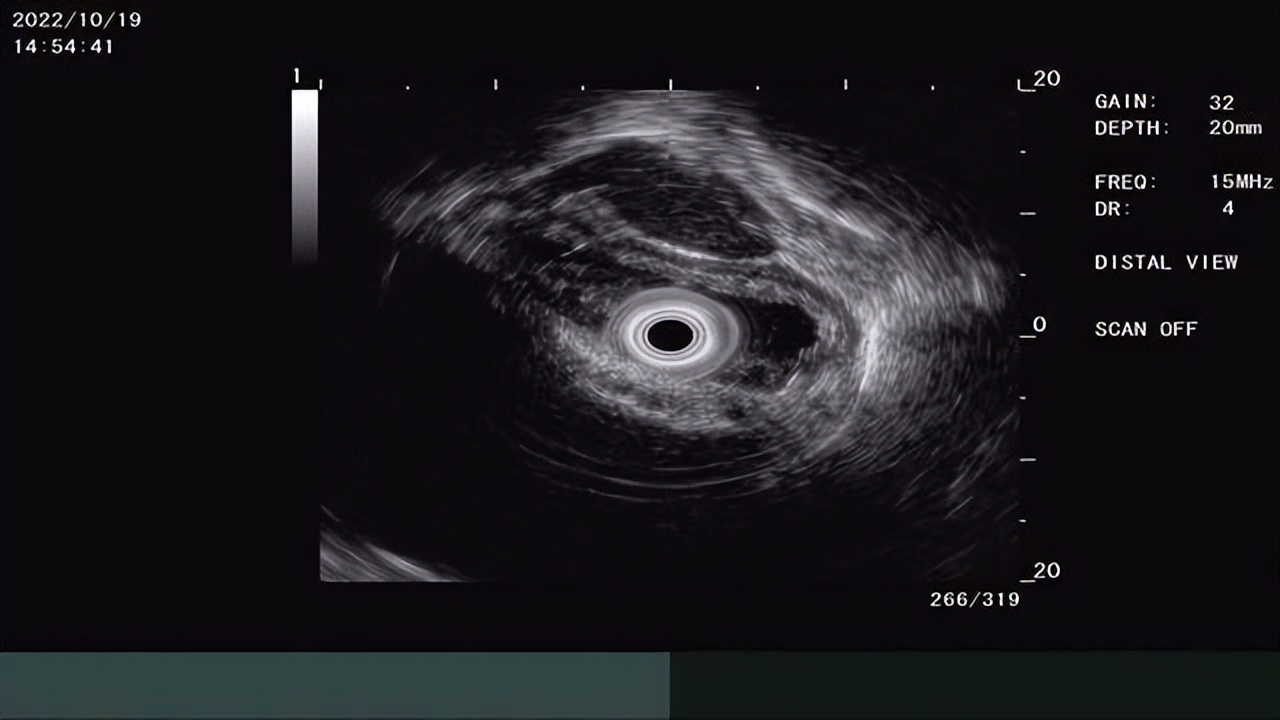

超声内镜下病变处层次清晰,未见异常回声影

消化内科韩霜主任为患者实施超声内镜检查,结合精查内镜及CT。经过仔细的术前评估,诊断为早期食管癌,未发生深浸润及远处转移,可以采用内镜下切除的方法。